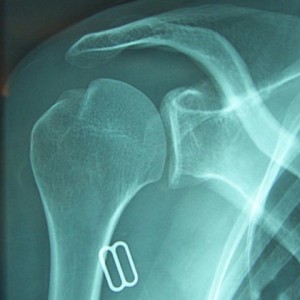

Epaule réduite avec encoche de Malgaigne

Malgré cela, votre articulation a tendance à se déboîter. A chaque fois que la tête de l’humérus sort complètement (luxation) ou partiellement (subluxation), elle abîme les éléments chargés de la garder en place. La luxation antérieure est de loin la plus fréquente (luxation postérieure (5%).